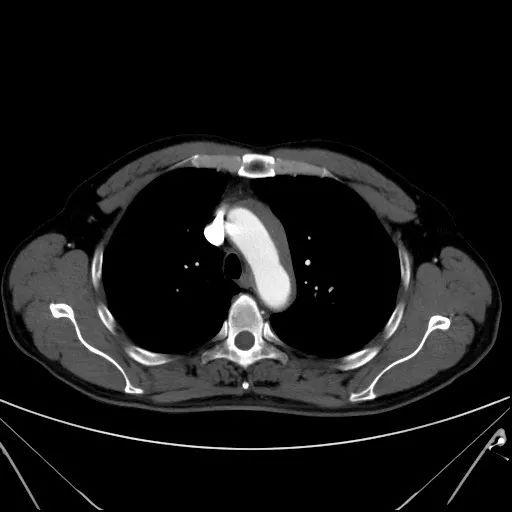

没有高血压病史,没有持续性剧烈胸痛,没有双上肢血压不对称,怎么会主动脉夹层了呢?加急做了一个主动脉CTA,回报:主动脉弓壁内血肿(图1)。此时耳鼻喉科的喉镜结果也回来了--左侧声带固定于旁正中位,左侧声带麻痹。

图1:主动脉弓血管周围环形包裹的低密度影即为主动脉壁内血肿,最厚处约12 mm

这位患者主动脉CTA明确可见主动脉壁环形增厚,最厚处12 mm,内膜钙化内移,主动脉管腔轻度受压,未及内膜片,因此IMH诊断明确;